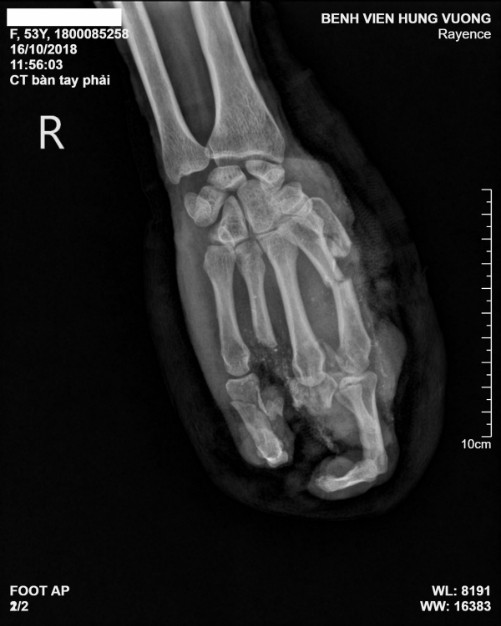

Ngày 16/10 bệnh nhân được các bác sĩ Bệnh viện Đa khoa Hùng Vương (Phú Thọ) vệ sinh vết thương và cầm máu. Kết quả chụp X-quang cho thấy bệnh nhân cụt ngón 3 và ngón 4, các ngón khác bị tổn thương trầm trọng, cơ gân dập toàn bộ. Bệnh nhân được bác sĩ phẫu thuật tạo hình bàn tay phải.

| Phim chụp X-quang bàn tay của bệnh nhân. |